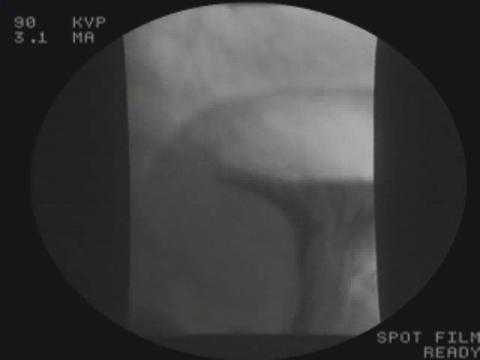

Рентгенологические исследования пищеварительного тракта с использованием бария

Рентгенологические исследования с использованием бария часто дают больше информации, чем стандартные рентгенологические исследования. Рентгенологические исследования проводят после того, как человек проглатывает барий в ароматизированной жидкой смеси или в виде покрытой барием пищи. На рентгенограммах барий выглядит белым и очерчивает пищеварительный тракт, показывая контуры и слизистую пищевода (полая трубка, ведущая из горла в желудок), желудка и тонкой кишки. Барий может накапливаться в аномальных участках, выявляя язвы, опухоли, закупорки и эрозии, а также увеличенные, расширенные вены пищевода.

Для определения положения бария можно делать рентгенограммы через небольшие интервалы. При использовании методики непрерывной рентгенографии, называемой рентгеноскопией, наблюдают за тем, как барий движется по пищеварительному тракту. При использовании этой методики врачи могут видеть, как функционируют пищевод и желудок, определить, нормально ли они сокращаются, и выяснить, не блокируется ли прохождение пищи по пищеварительному тракту.